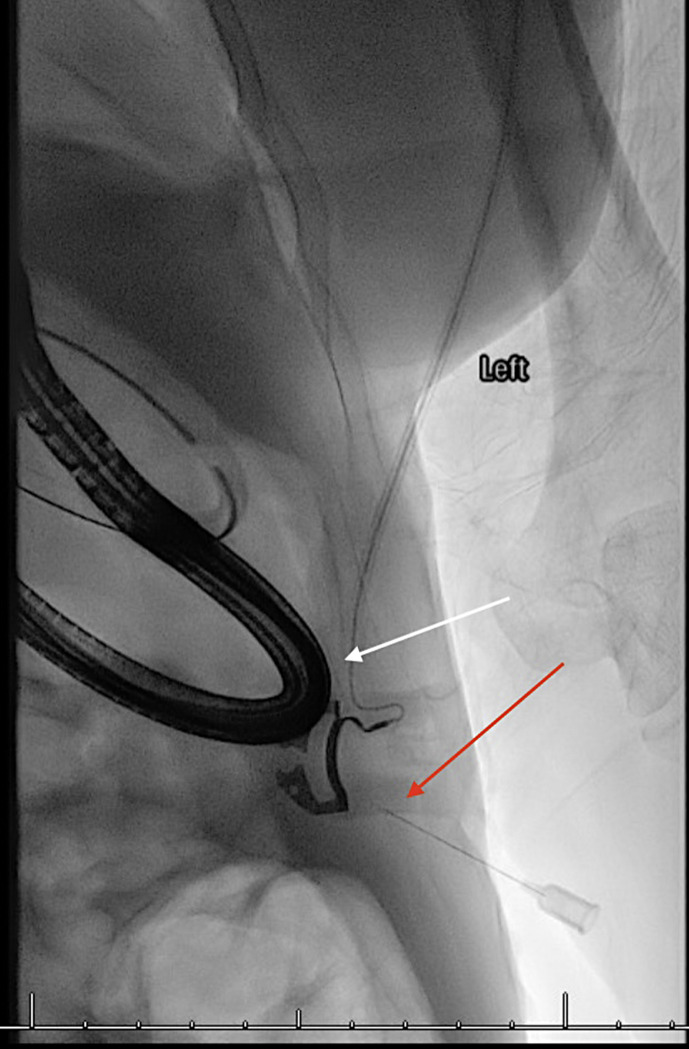

Introduction: We report the case of a 60-year-old female with a history of perforated gastric ulcer, abdominal abscesses, enterocutaneous fistula, and small bowel obstruction requiring durable gastric decompression prior to delayed fistula takedown. The patient had contraindications to or failed attempts at traditional gastrostomy approaches (surgical, endoscopic, interventional radiology).

Case report: Gastrostomy was successfully performed via a novel technique combining interventional radiology and endoscopic placement.